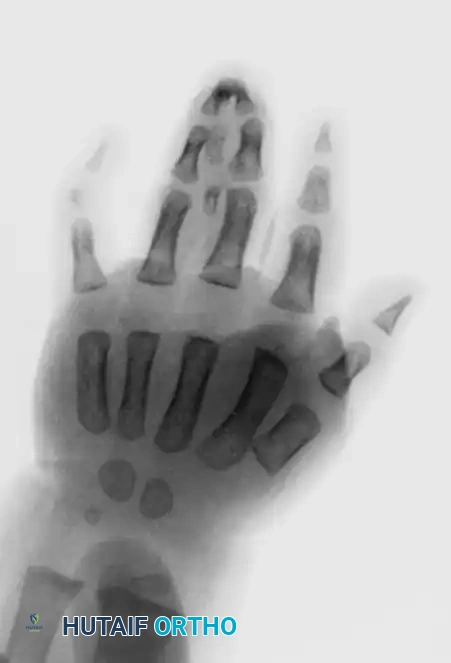

Image

Figure: Simple syndactyly, palmar view. Fingers are bridged only by skin and soft tissues.

Figure: Simple syndactyly, dorsal view.

Figure: Radiograph of simple syndactyly. Note the angular deformity beginning to develop in the ring finger.